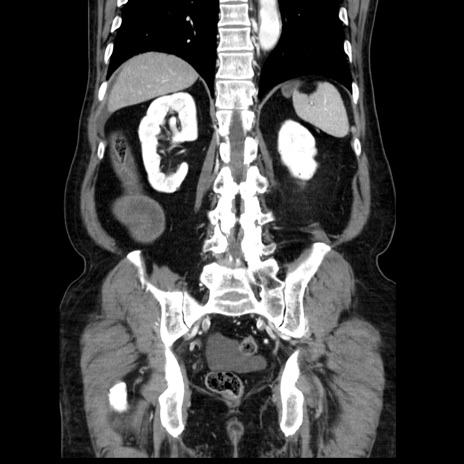

症例30(冠状断像)

【症例】80歳代男性

【主訴】臍周囲痛

【現病歴】約6時間前から臍下部痛が出現。次第に腹部膨隆・背部痛も生じてきたため来院。背部痛の場所は変化しない。

【身体所見】意識清明、BT 36.3℃、BP  131/87mmHg、P 87bpm、SpO2 100%(RA)、臍周囲自発痛・圧痛あり、反跳痛なし、自発痛部位に一致して板状硬あり、腹部膨隆、腸雑音減弱、CVA tenderness両側陰性。